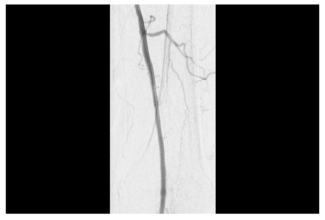

The objective of this study was to demonstrate the feasibility of subintimal implantation of interwoven nitinol stents in CLTI patients with chronically occluded superficial superior artery and popliteal stents.